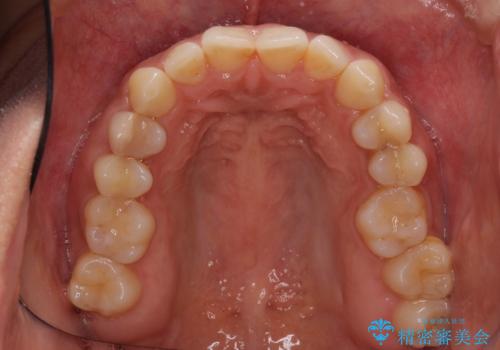

沖縄から飛行機で通院 インビザラインによる矯正治療

- 患者様

- 30代女性

- 矯正装置

- インビザライン

- 治療期間

- 3年8ヶ月

- 定期的に東京に来るので、沖縄から矯正治療で通院したいとのことで来院された患者様です。

歯列不正は軽度であったので、応急処置の少ないインビザラインにて矯正治療を行うこととしました。

今後もむし歯治療が必要となるため、日程を調整して沖縄から通院されるとのことでした。